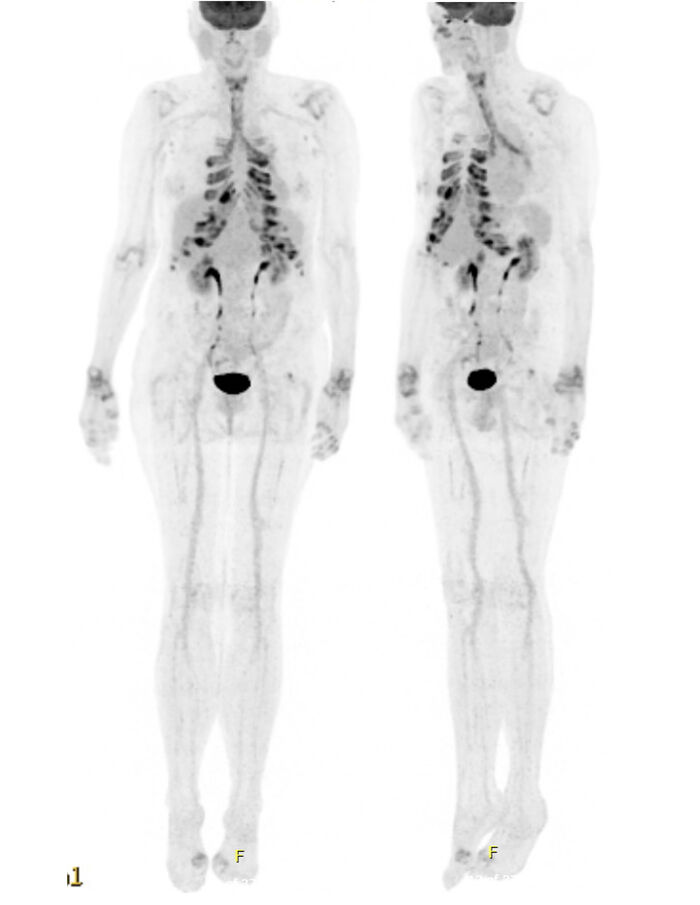

Einkenni eru afar fjölbreytt og fara eftir því hvaða líffæri verða fyrir áhrifum. Í tilfelli mánaðarins má sjá útbreiðslu bólgunnar á mynd úr jáeindaskannanum og tengja við einkenni sjúklingsins. Við jáeindaskönnun er í einfölduðu máli gefið sporefni tengt við glúkósa sem leitar síðan í svæði sem eru með mikla notkun glúkósa. Sporefnið hefur þannig mikla upptöku í heila og hjarta og aukna upptöku í illkynja sjúkdómum og bólgusjúkdómum.

Á mynd 1 er til staðar bólga í rifbrjóski við bringubein (brjóstverkur), barka (ertingsastmi), barkakýli (hæsi) og liðum (liðbólgur í úlnliðum, hægri olnboga, öxlum og smáliðum handa). Ekki er til staðar bólga og roði í ytra eyranu eða í nefbrjóski. Bólga og eyðing brjósks í öndunarvegum getur valdið þrengingu á loftvegum eða samfalli á loftvegum (tracheomalacia) sem útsetur fyrir endurteknum sýkingum eða öndunarbilun. Sjúkdómur í miðlægum öndunarvegi er helsta dánarorsök sjúklinga með RP. Í augum getur komið hvítubólga (scleritis) eða æðahjúpsbólga (uveitis) sem getur leitt til sjónskerðingar. Stór hluti sjúklinga fær heyrnartap á einhverjum tímapunkti sjúkdóms vegna áhrifa á innra, mið- eða ytra eyra. Í hjarta- og æðakerfi getur komið ósæðarbólga og skemmdir á hjartalokum. Almenn einkenni geta fylgt hávirkum sjúkdómi, svo sem hiti, þreyta og þyngdartap. Í körlum þarf að íhuga UBA1-stökkbreytingar og VEXAS-heilkenni.

Vegna alvarlegrar sjúkdómsmyndar var hafin meðferð með háskammta barksterum og sterasparandi metótrexati. Meðferð með adalimumab var hafin snemma vegna alvarleika sjúkdóms þar sem tilfellalýsingar og tilfellaraðir hafa sýnt góð áhrif á loftvegabólgu og sterasparandi áhrif.3 Meðferð tafðist töluvert fyrstu mánuðina vegna tíðra öndunarfærasýkinga. Bætt var við langvirku andkólínvirku innöndunarlyfi, acetýlcysteini og fyrirbyggjandi azítrómýcíni. Notað var salbútamól og íptratrópíum brómið í innúðatæki, cíprófloxacín og auknir stera við öndunarfærasýkingar. Við ritun þessarar greinar hefur meðferð með metótrexat og adalimumab verið stöðug í sex mánuði. Sjúklingur þurfti háa skammta af barksterum þar til þessar meðferðir hófust en þá var unnt að minnka niður í 5mg prednisólón daglega. Klínísk einkenni höfðu minnkað mikið en enn var töluverður ertingur í barkanum. Eftirlitsmyndataka í jáeindaskanna sýnir nú einungis væga upptöku sporefnis í barkakýli en enga í liðum, barka né bringubrjóski. Ekki fannst klár skýring á kviðverkjunum en engin köst hafa komið síðan meðferð hófst.

Mynd 1. Yfirlitsmynd úr jáeindaskanna við sjúkdómsgreiningu. / FDG-PET

survey image at diagnosis